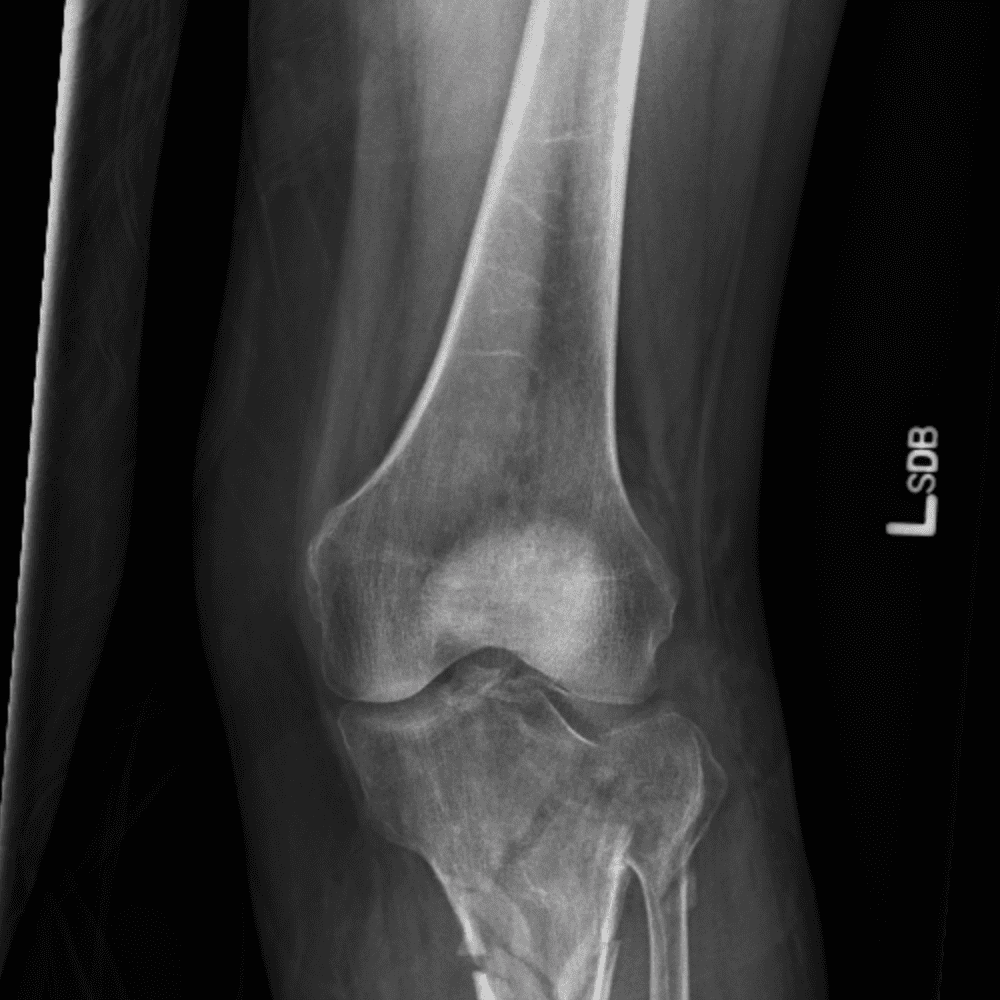

Simula o plantão incluindo casos sutis ou difíceis e alguns normais.